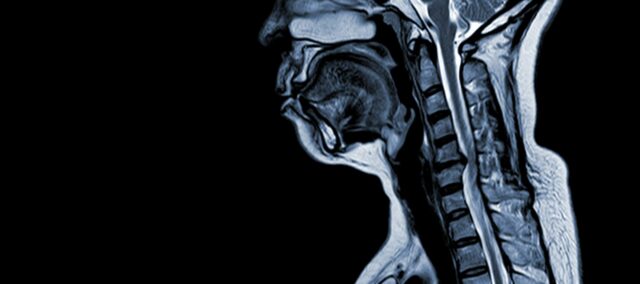

A nyaki spondyloticus myelopathia (CSM) egy neurológiai állapot, ami felnőtteknél a gerincvelő sérülésének vezető oka. Egyszerűen fogalmazva, a nyaki gerincvelő összenyomódását vagy károsodását jelenti, elsősorban a nyaki csigolyákat érintő természetes öregedési folyamat miatt. A „myelopathia” kifejezés a görög „myelon” szóból származik, ami „gerincvelőt” jelent, és a „pathos” szóból, ami „betegséget” jelent.

- Porckorong degeneráció (előboltosuló porckorong): A CSM gyakran a nyaki gerincben lévő csigolyaközi porckorongok degenerációjával kezdődik, melynek hatására azok előboltosulnak vagy betüremkednek a gerinccsatornába.

- Subperiostealis csontképződés (a gerinccsatorna ventrális oldalán): A fokozott mechanikai stressz hatására a szervezet új csontszövetet képez a gerinccsatorna elülső (ventrális) oldalán, ami potenciálisan szűkítheti a gerincvelő számára rendelkezésre álló teret.

- A hátsó longitudinális szalag elcsontosodása: A hátsó longitudinális szalag elcsontosodhat, megkeményedhet és elmeszesedhet, ami hozzájárul a gerinccsatorna szűkületéhez.

- Ligamentum Flavum hipertrófiája: A Ligamentum Flavum hipertrófiája miatt megvastagszik és kevésbé lesz rugalmas, tovább szűkítve a gerinccsatornán belüli teret és összenyomva a gerincvelőt.

Ezek a strukturális változások együttesen a gerinccsatorna összenyomódásához és szűkületéhez vezetnek, ami a CSM jellegzetes tüneteit és szövődményeit eredményezi. E kockázati tényezők felismerése és a patofiziológiai mechanizmusok megértése elengedhetetlen a prevencióhoz és a kezeléshez. A korai diagnózis és a megfelelő beavatkozások kulcsfontosságúak e strukturális elváltozások gerincvelőre gyakorolt hatásainak enyhítésére.